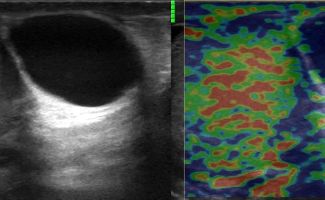

Η μελέτη με Έγχρωμο Doppler παρέχει κρίσιμες πληροφορίες σχετικά με την αγγείωση των όρχεων, ανιχνεύοντας αποκλεισμούς συστροφής ή φλεγμονές, όπως η ορχίτιδα.